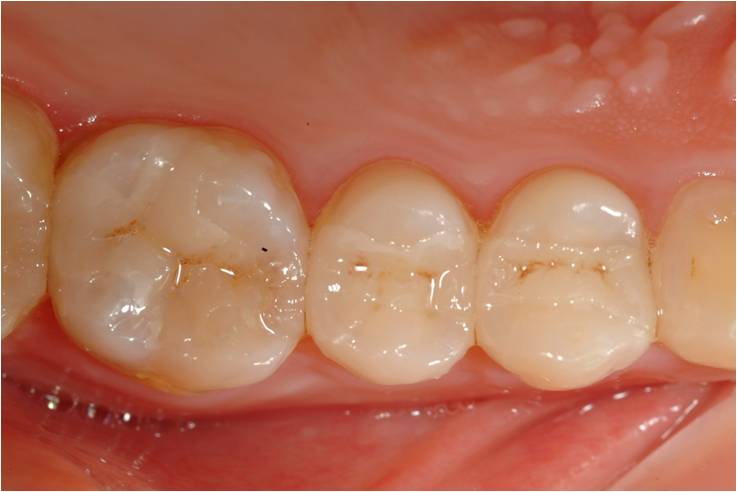

黏著後狀態